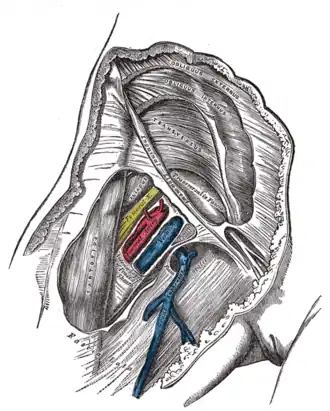

Right femoral sheath laid open to show its three compartments | |

Femoral sheath encloses the upper 4 cm of the femoral vessels. Its contents are shown below (from lateral to medial):

- Femoral branch of the genitofemoral nerve - occupies the lateral compartment of the femoral sheath along with femoral artery. It supplies the skin over the femoral triangle.[2]

- Femoral artery and its branches - It emerges from the base of the femoral triangle at the mid-inguinal point (midpoint between the anterior superior iliac spine and the pubic symphysis of the pelvic bone) and exits through the apex of the triangle into the adductor canal.[2]

- Femoral vein and its tributaries - The vein lies medial to the femoral artery at the base of the triangle but as it approaches the apex of the triangle, it lies posteromedially to the femoral artery. It receives drainage from great saphenous vein, circumflex veins, and veins corresponding to the branches of the femoral artery here.[2]

- Deep inguinal lymph nodes - It lies deep to the deep fascia, medial to the upper part of the femoral vein, inside the femoral canal (medial compartment of the femoral sheath). Cloquet's node (also known as Rosenmuller's node) also lies in this canal. It receives lymphatic drainage from superficial inguinal lymph nodes, lymphatic drainage from the glans penis or clitoris, and from the deep lymphatics of the lower limb.[2]